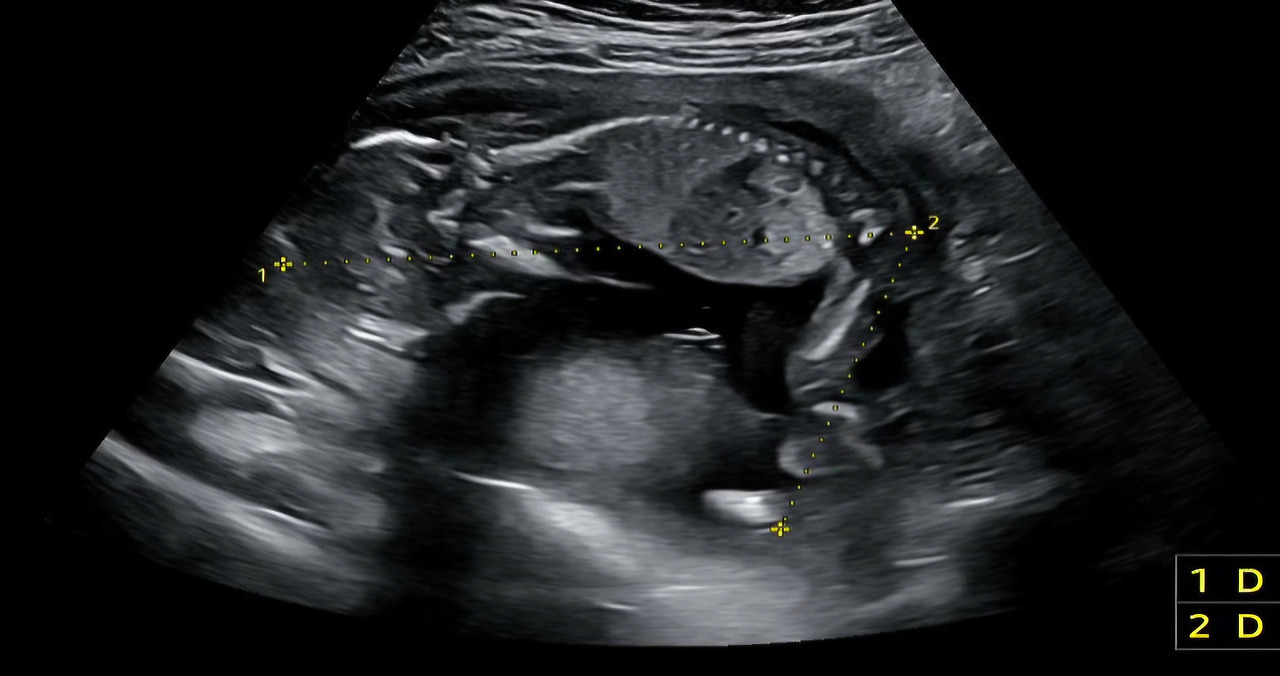

25년 10월 14일 초음파. 처음 보는 링링의 엎드린 모습.